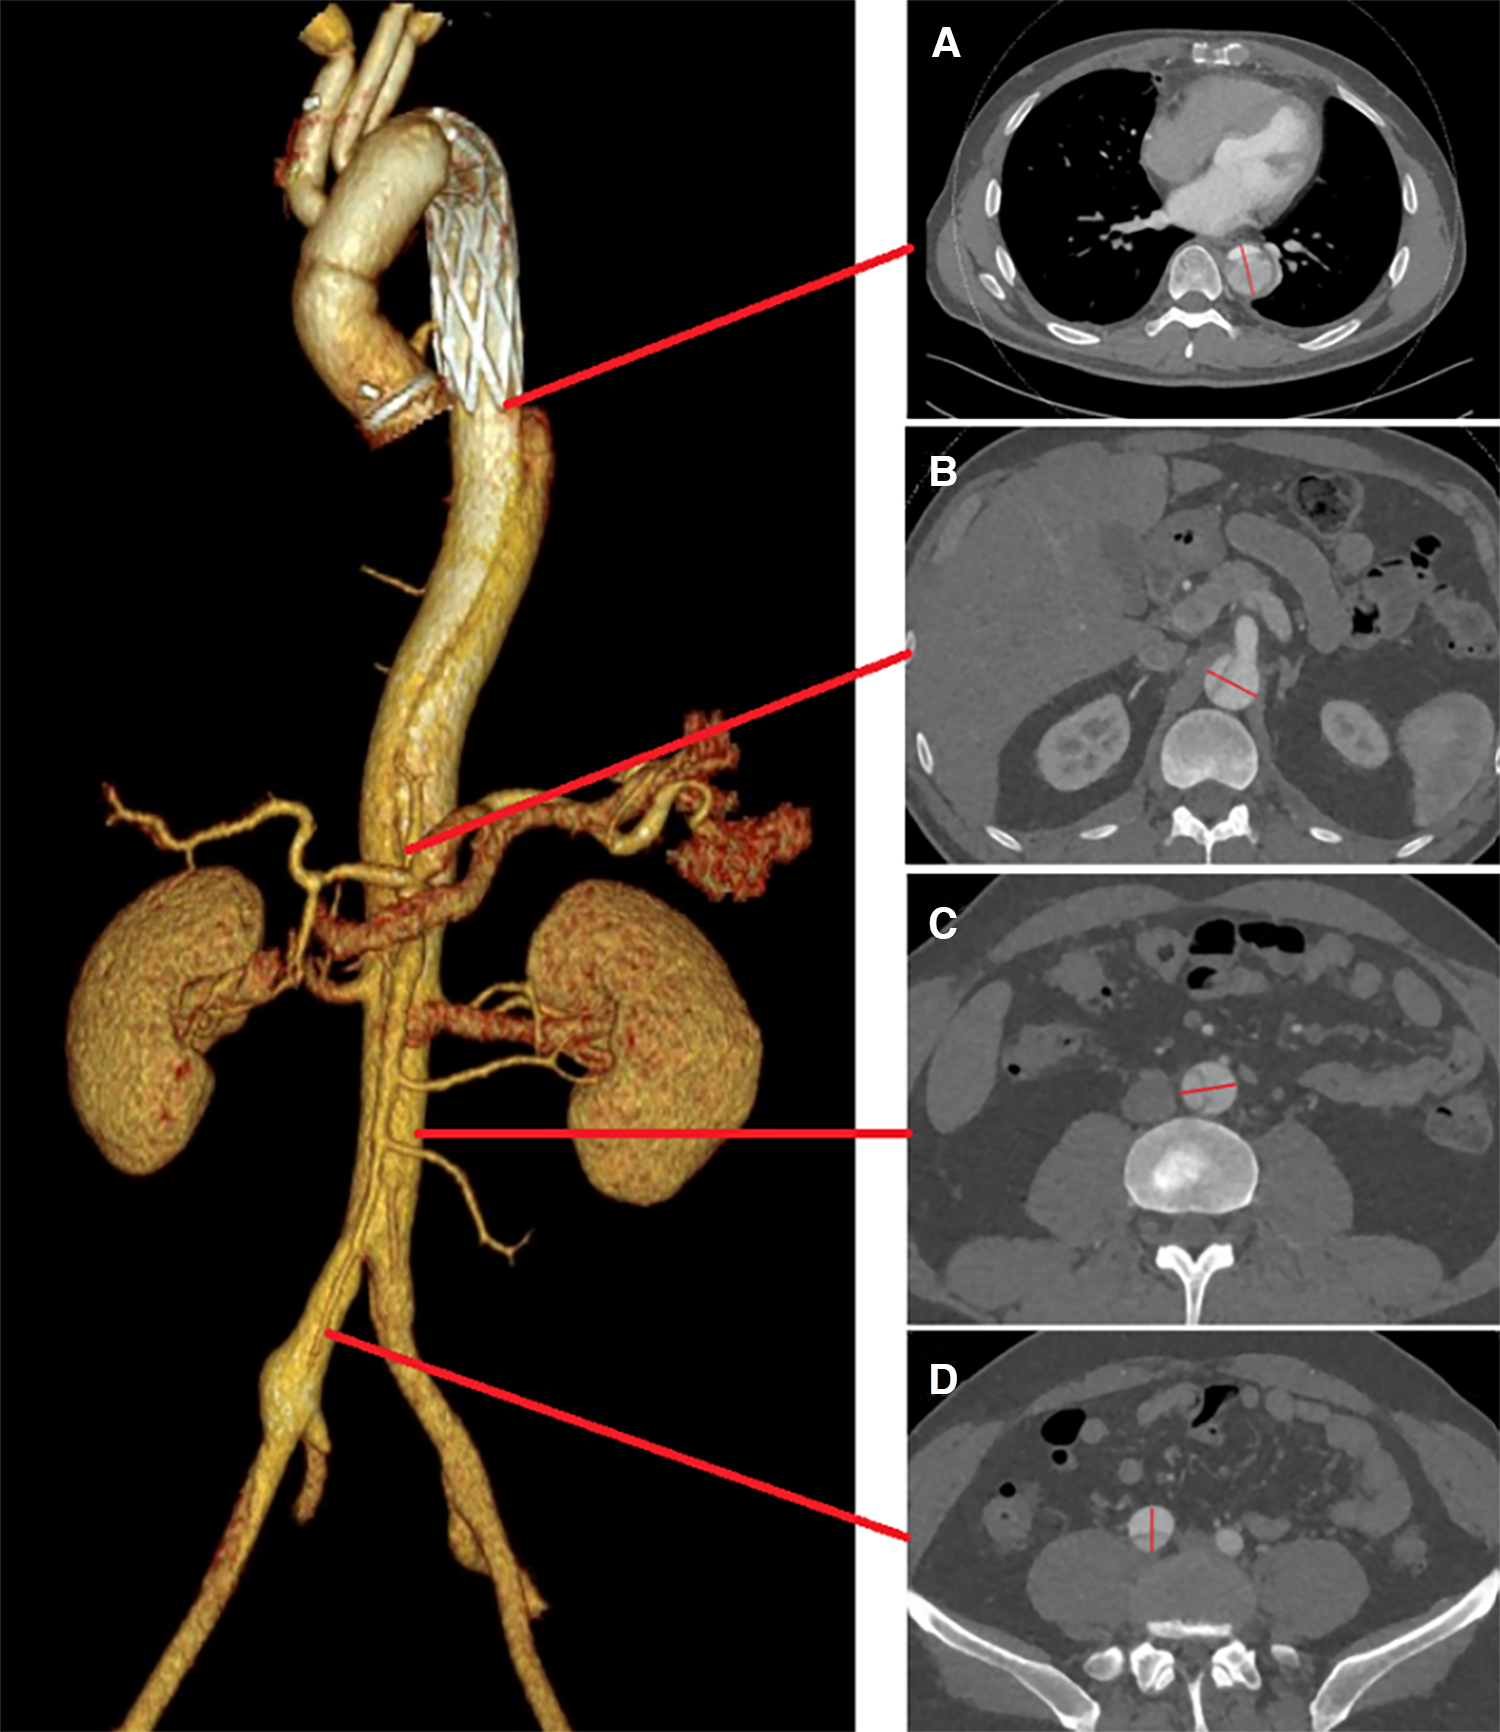

The primary outcome of interest was the incidence of all-cause mortality in patients with RAD during the follow-up period. Secondary outcomes included events such as occlusions of visceral branches, the necessity for additional interventions, and incidents categorized as severe adverse events. A comprehensive preoperative morphological assessment was performed, along with regular evaluations at follow-up intervals. This involved precise measurements of TL and FL diameters. Morphological indices were measured at four anatomical planes: the distal end of the primary stent, the plane at the celiac trunk opening, 5 cm below the renal arteries, and 1 cm below the iliac artery bifurcation (Figure 1).

Figure 1

True and FL diameters were measured using a straight line that passes through the midpoint of the intima and the center of the circle. Measurements were taken at the following locations: (A) the distal end of the primary stent; (B) the celiac trunk opening; (C) 5 cm below the renal arteries; (D) 1 cm below the iliac artery bifurcation.